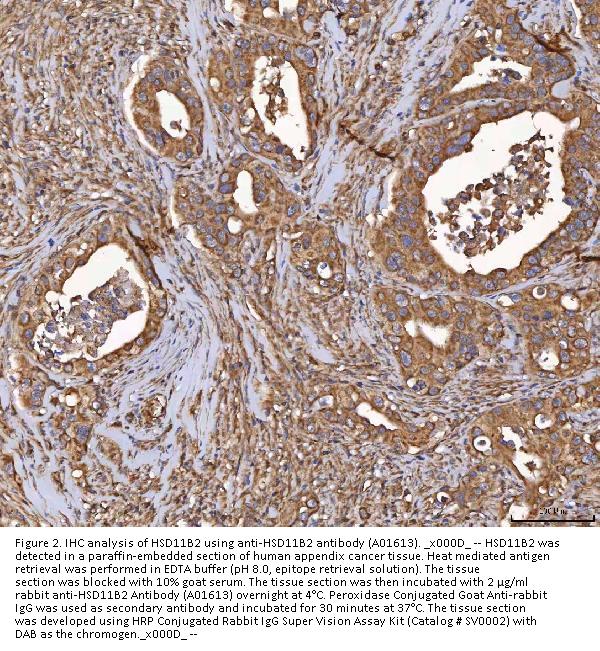

Immunohistochemistry(Paraffin-embedded Section), 2-5 μg/ml, Human

Boster Bio Anti-HSD11B2 Antibody Picoband® catalog # A01613. Tested in ELISA, Flow Cytometry, IF, IHC, WB applications. This antibody reacts with Human. The brand Picoband indicates this is a premium antibody that guarantees superior quality, high affinity, and strong signals with minimal background in Western blot applications. Only our best-performing antibodies are designated as Picoband, ensuring unmatched performance.